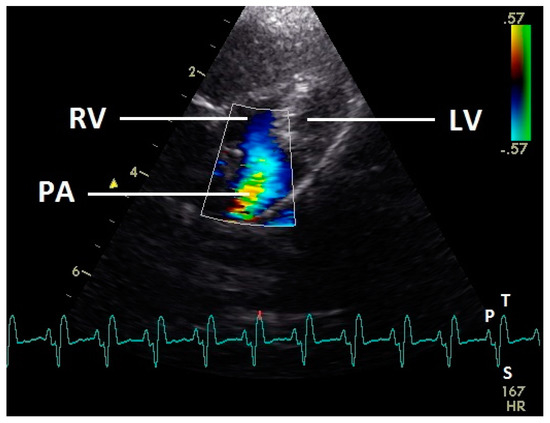

3.6. Right Ventricular Ejection

During systole (ascending part of S wave to descending part of T wave of ECG), a blue flow signal was seen in the right ventricular outflow tract and pulmonary artery (Figure 10). In all pigeons aliasing occurred in the pulmonary artery with our settings. A regurgitation of the right AV valve was not seen.

Figure 10.

Color Doppler image of the right ventricle in the systole. The blood ejection from the right ventricle in the pulmonary artery is visible (blue signal). The blue flow signal is aliased in the pulmonary artery (wrong direction: red instead of blue of the color Doppler signal in the pulmonary artery). LV: left ventricle; RV right ventricle; PA: pulmonary artery; HR: heart rate. Electrocardiogram: P: P wave, S: S wave, T: T wave. The color scale on the right of the image is calibrated in m s−1.